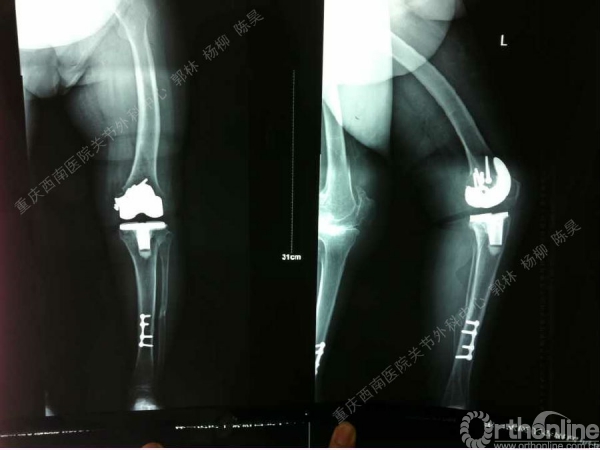

导读:文中,来自重庆西南医院的郭林教授为大家介绍了股骨冠状位关节外畸形的TKA的相关知识,并详细阐述了关节外畸形的概念、诊断、关节内滑移截骨技术等相关内容。

滑移截骨纠正关节外畸形